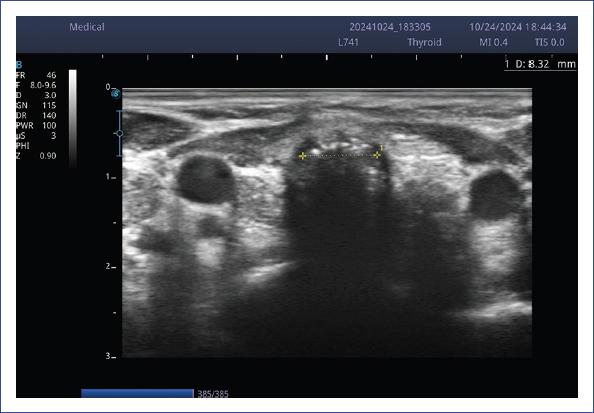

El IPFS y el LACWD se midieron con ultrasonido portátil Sonoscape E2 y transductor lineal (7-15 mHz) usando una configuración para tejidos blandos. Dicha medición se realizó por un intensivista pediatra ecografista crítico durante el protocolo de retiro del ventilador. Se obtuvieron tres mediciones y se promediaron. Las estructuras que se visualizan en la ecografía laríngea se muestran en la figura 1. La técnica de medición del IPFS se explica en la figura 2, y la medición del LACWD se explica en las figuras 3 y 4.

Figura 2 Medición del espacio libre peritubo intracricoideo. Con el paciente en decúbito supino e hiperextensión, se coloca el transductor en orientación transversal y se identifica una imagen hipoecogénica en forma de C, correspondiente al cartílago cricoides (rojo). A continuación, se localiza la línea hiperecogénica en la superficie posterior del cartílago cricoides, correspondiente a la interfaz de aire (verde), marcando los dos bordes internos del cartílago cricoides (amarillo), la cual se mide transversalmente y se resta el diámetro externo del tubo endotraqueal, que es proporcionado en el empaque por el fabricante.